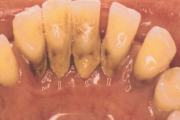

Krooniline parodontiit

Krooniline parodontiit on mikroobide poolt põhjustatud hammaste tugikudede põletik, mille tulemusena tekib progresseeruv alveolaarluu (nähtav röntgenograamil) ja periodontaalligamendi destruktsioon, igemetaskute moodustumine, igeme retsessioon või mõlemad kahjustused kombineeritult. Loe edasi »

- puudulik suuhügieen (5)

- igemepealne hambakivi (5)

- igemealune hambakivi (4)